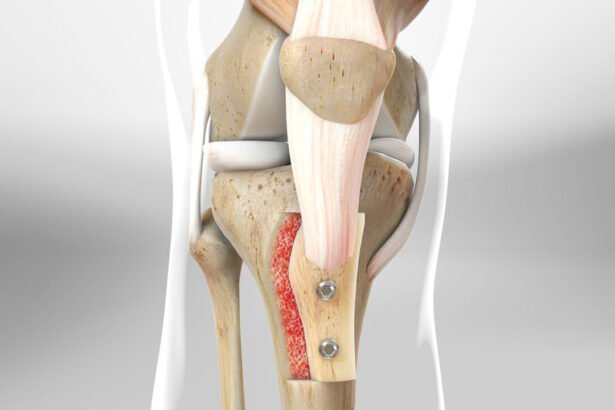

Knee Realignment Osteotomy